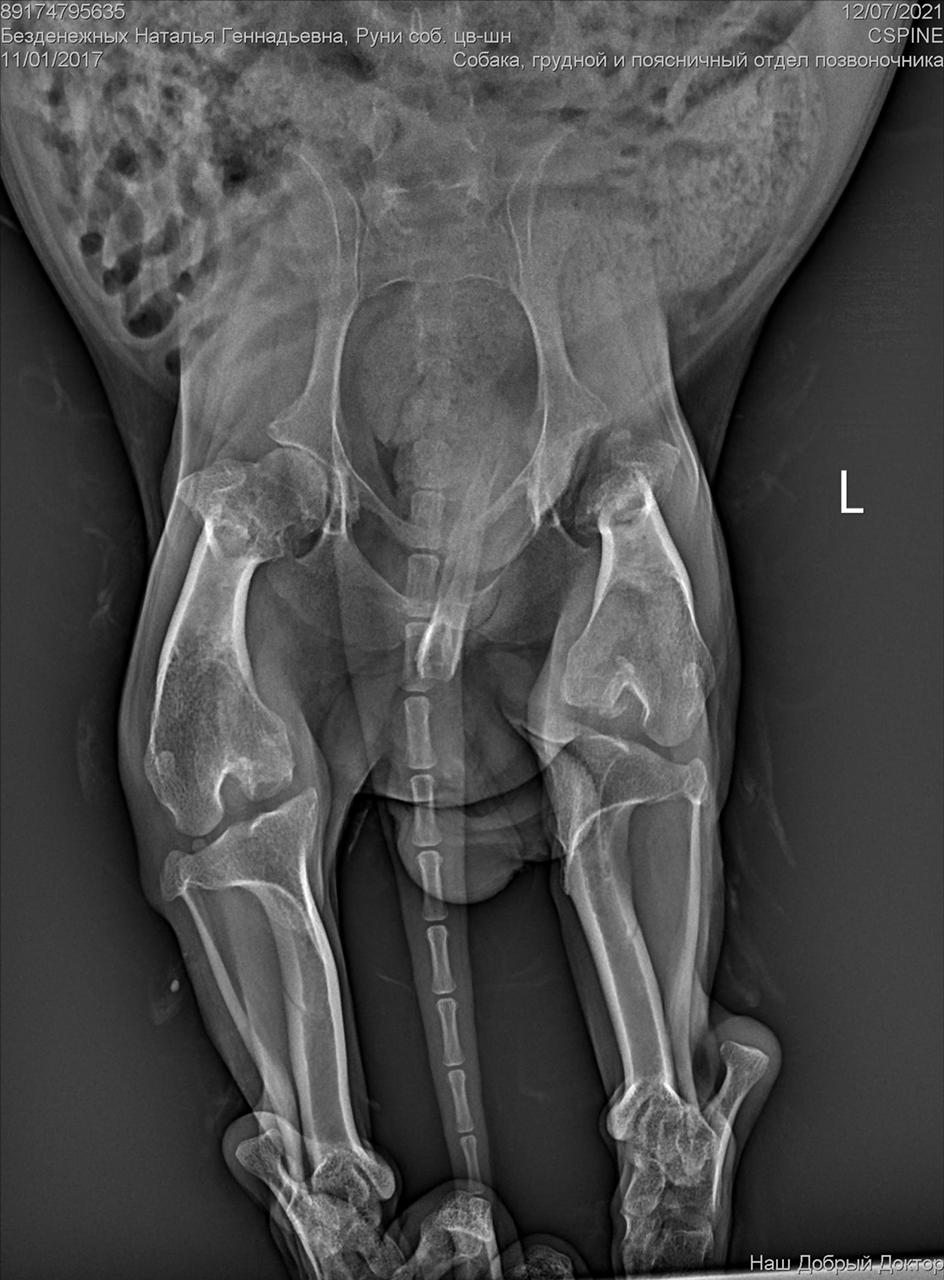

Рентген конечно.....

А нельзя по клиникам уточнить, кто делал резекцию шейки бедра цвергу? Млжет таких хирургов и не так много в городе?

Была травма однозначно. Удалена головка бедра. Мышц нет.

И с позвоночником проблемы. Врачи говорят операции тут не помогут. Если только реабилитация , массаж. Восстановить как то мышцы